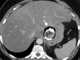

Trauma with gastric perforation

Gastrointestinal perforation, also known as ruptured bowel, is a hole in the wall of part of the gastrointestinal tract. The gastrointestinal tract includes the esophagus, stomach, small intestine, and large intestine. [Source: Wikipedia ]